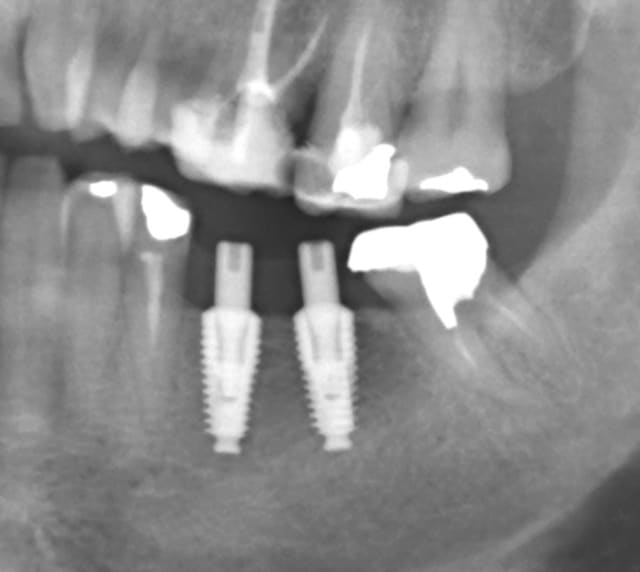

Mise en place de 2 implants IDI Idcam , très bonne impression , forage hypersimplifié ( 4 forets pour du 5.2),et sécurisé grâce aux forets à butée, excellente sensations lors de la mise en place à la clef à cliquet à la position souhaité / à l'os crestal.